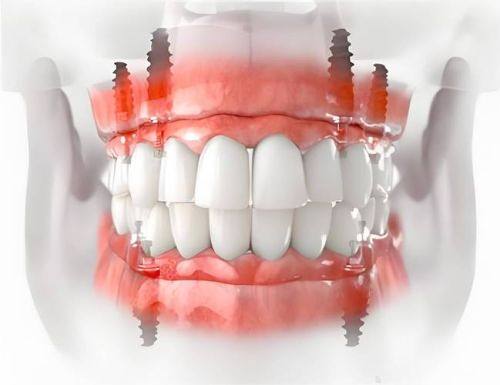

种牙打桩后几天拆线是特别多种牙患者关心的问题。种牙打桩后拆线时间不是固定的,它和伤口愈合情况密切相关。了解种牙打桩后拆线的时间以及修复过程和注意事项,能帮助患者更好地应对种牙后的修复阶段,减少不必要的担忧。接下来,我们就详细探讨种牙打桩后拆线的相关内容,让你对整个修复过程有更清晰的认识。

种牙打桩后几天拆线这个问题,需要根据个人的伤口愈合情况来确定,一般是7天或者10天。了解种牙打桩后的修复过程和注意事项,能让患者在种牙后更好地照顾自己,促进伤口的愈合。希望患者们在种牙后都能严格按照医生的建议进行护理,顺利度过修复阶段,拥有健康的牙齿。如果你对种牙打桩后拆线还有其他疑问,建议及时询问专精的口腔医生。